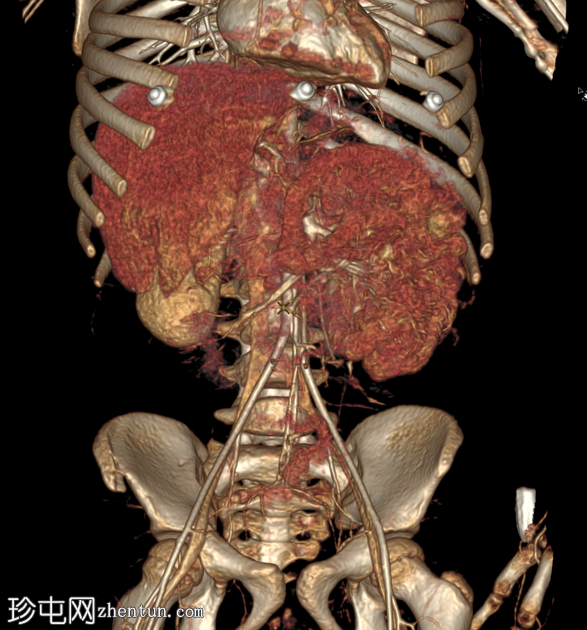

容积重建

C+动脉期

AAST IV级肝撕裂伤,伴有大面积不规则肝损伤,累及V段(轴向、冠状、矢状)。

撕裂伤区域内未见活动性造影剂外渗。

可见中等量腹腔积血。

右髂前骨骨折。

无气腹。